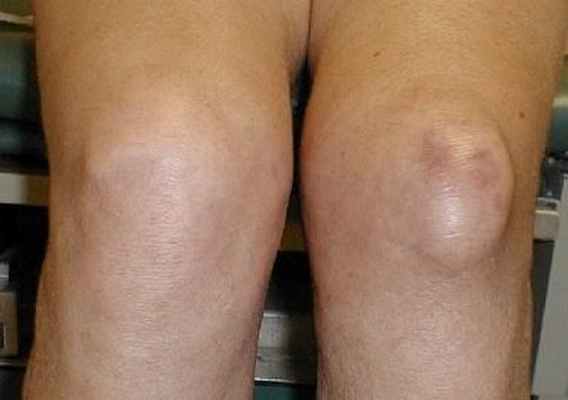

Рисунок 4. Киста Бекера.

ж) Пальпация сумки икроножной и полусухожильной мышц. Сумка икроножной и полусухожильной мышц расположена в подколенной ямке. В норме она не пальпируется, однако становится доступна пальпации при воспалении. Это состояние известно как киста Бекера. Кисту можно легко увидеть и пропальпировать, если коленный сустав разогнут. Она подвижна и обычно безболезненна (рис. 4). Киста Бекера может образовываться при любом объеме выпота в коленном суставе.